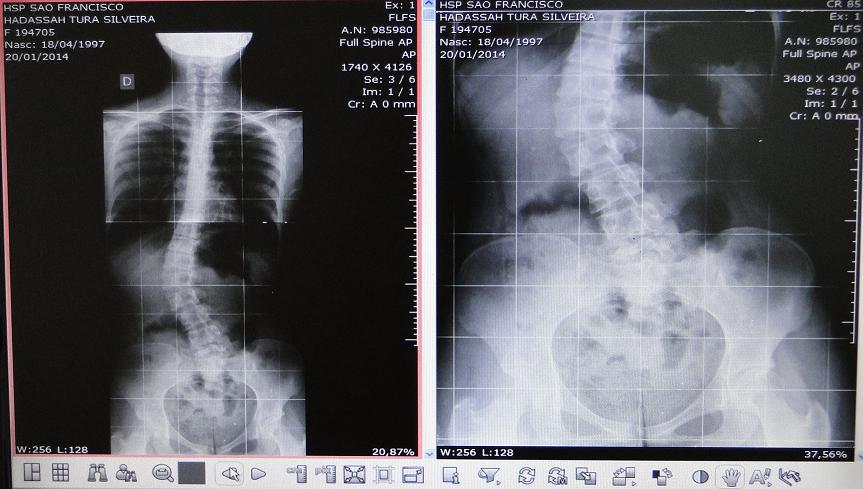

O Hospital São Francisco de Concórdia realizou um procedimento cirúrgico inédito na região no último dia 21. Uma operação para correção da Escoliose Idiopática do Adolescente foi feito uma paciente de 16 anos, moradora do município de Xaxim. A cirurgia foi realizada pelo ortopedista pediátrico, doutor Carlos Augusto Araújo dos Santos, com o auxílio do também médico ortopedista doutor Roberto Longarai Daher.

A escoliose é o desvio lateral da coluna que acomete crianças e adolescentes entre 10 e 18 anos de idade. A prevalência é de 1,5% a 3% da população, sendo mais comuns em indivíduos do sexo feminino.